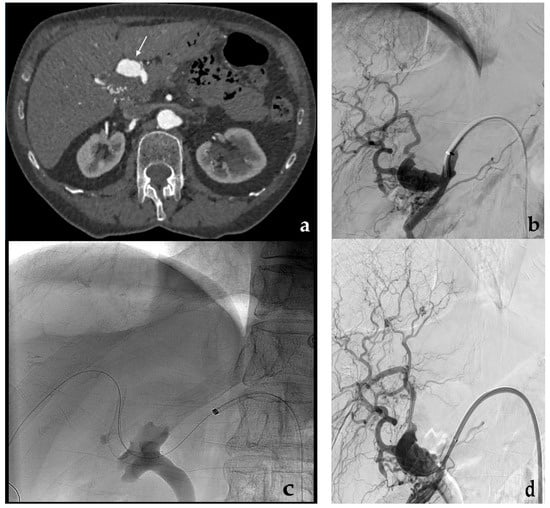

3.1. Coil Embolization

- Koganemaru, M.; Abe, T.; Nonoshita, M.; Iwamoto, R.; Kusumoto, M.; Kuhara, A.; Kugiyama, T. Management of visceral artery embolization using 0.010-inch detachable microcoils. Diagn. Interv. Radiol. 2014, 20, 345–348. [Google Scholar] [CrossRef] [PubMed]

- Yasumoto, T.; Osuga, K.; Yamamoto, H.; Ono, Y.; Masada, M.; Mikami, K.; Kanamori, D.; Nakamura, M.; Tanaka, K.; Nakazawa, T.; et al. Long-term outcomes of coil packing for visceral aneurysms: Correlation between packing density and incidence of coil compaction or recanalization. J. Vasc. Interv. Radiol. 2013, 24, 1798–1807. [Google Scholar] [CrossRef] [PubMed]